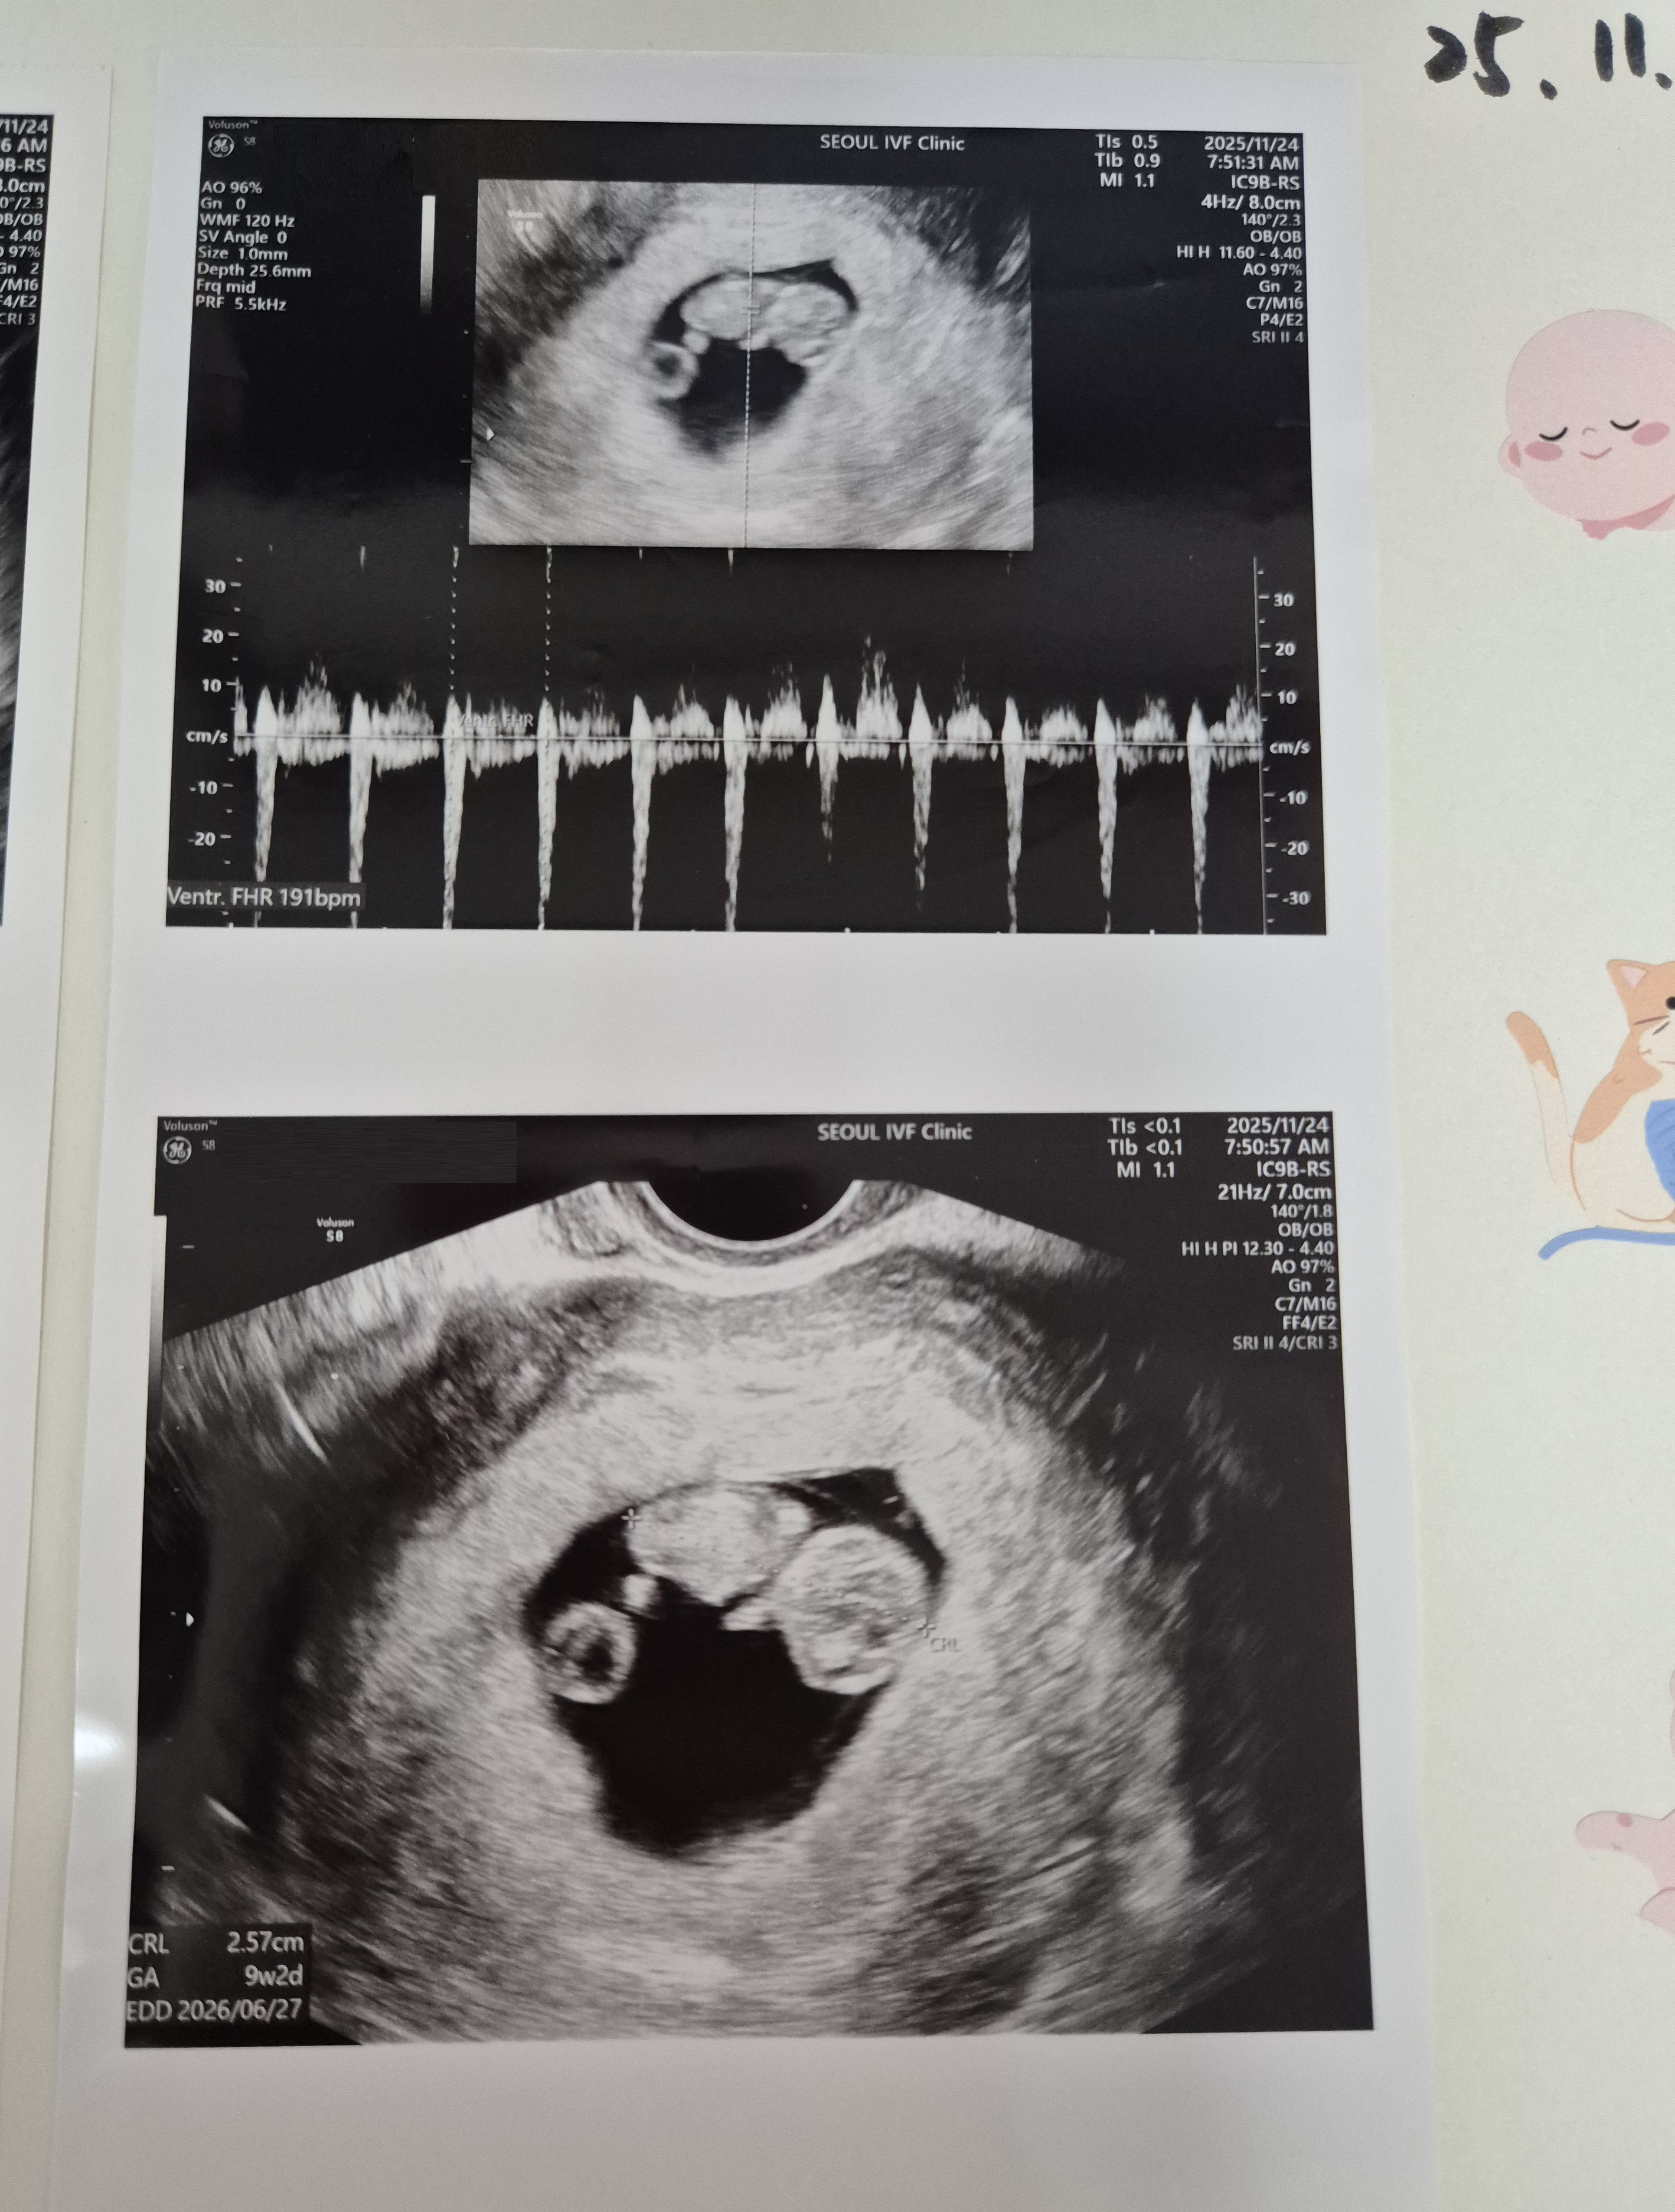

| 가슴 떨리는 임신 이야기를 공유해 주세요. | 태아의 심장소리를 처음 들었을 때, 그 순간의 감동은 말로 다 표현할 수 없을 만큼 벅찼습니다. 긴 불안과 기다림 끝에 생명을 품고 있다는 사실이 실감 나는 순간이었습니다. |

| 치료 도중 느꼈던 가장 기뻤던 순간과 절망적인 것들은 무엇인가요? 잊지 못할 경험이 있나요? | 가장 힘들었던 기억은 8주 차에 계류유산을 경험했을 때였습니다. 반면, 심장소리를 다시 들었을 때와 난임병원을 졸업하던 날은 평생 잊지 못할 가장 기쁜 순간으로 남아 있습니다. |

| 서울IVF여성의원의 난임 치료에 대해 말씀해 주실 것이 있나요? | 긴 치료 과정 동안 불안하고 지칠 때도 많았지만, 의료진 분들의 따뜻한 손길과 지속적인 응원이 큰 힘이 되었습니다. 그 덕분에 11주 4일 된 아기를 품고 이 순간을 맞이할 수 있었다고 생각합니다. |